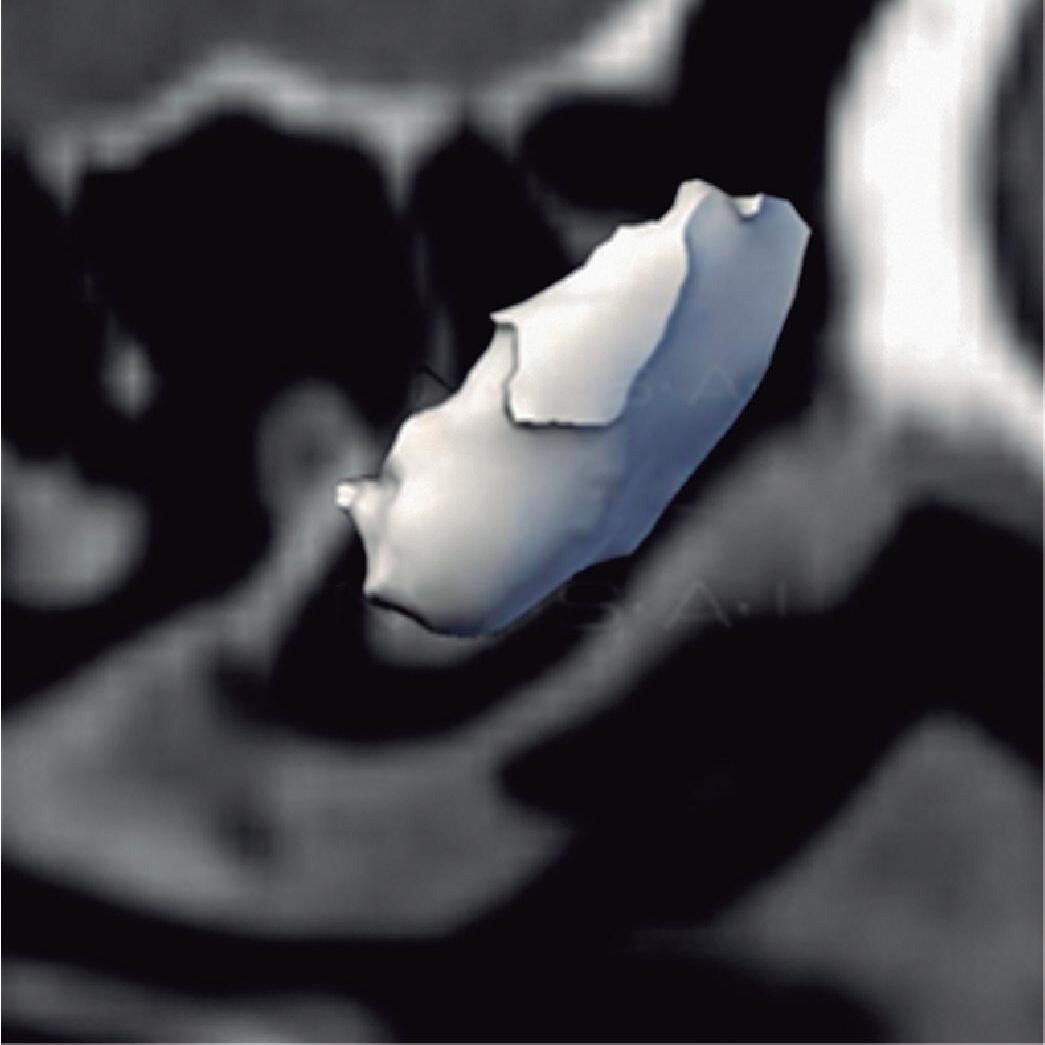

1-8. Osso etmoidal e seio etmoidal (amarelo) observar o aspecto incompleto do teto do seio etmoidal que será coberto pelo osso frontal (rosa).

Este complexo anatômico chamado seio etmoidal, controla a pressão e o fluxo aéreo que penetra nos verdadeiros seios paranasais e pode ser interpretado como um sistema de câmaras aerodinâmicas de baixa pressão cuja topografia particular faz dele o centro anatomofuncional do aparelho rinossinusal.